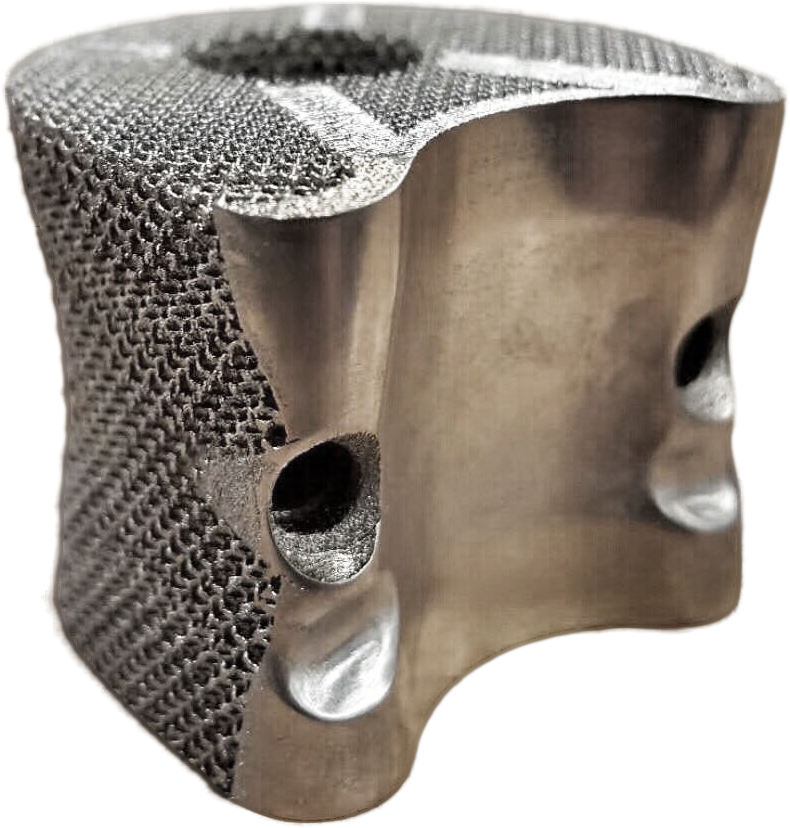

就不说什么长篇大论了,先看看我们手术植入的植入物

就是这个玩意,我们在设计这个金属植入椎体的时候花了很多时间,前前后后共除了100多套方案,制作了数十个模型进行研讨,最终确定下来为这个方案。

就是这个玩意,我们在设计这个金属植入椎体的时候花了很多时间,前前后后共除了100多套方案,制作了数十个模型进行研讨,最终确定下来为这个方案。

这个植入物的是根据病人的脊柱CT扫描数据来进行构建出精准的3D图像,再以此来设计出最适合病患的个性化植入物。

手术主刀医生在这个案例提出了海绵状的微孔结合拓扑框架结构,这种内嵌拓扑框架金属“骨小梁”,有利于相邻正常脊椎的骨细胞长入其中,最终实现骨融合,又保证了椎体的整体力学性能。

就不说什么长篇大论了,先看看我们手术植入的植入物

就是这个玩意,我们在设计这个金属植入椎体的时候花了很多时间,前前后后共除了100多套方案,制作了数十个模型进行研讨,最终确定下来为这个方案。

就是这个玩意,我们在设计这个金属植入椎体的时候花了很多时间,前前后后共除了100多套方案,制作了数十个模型进行研讨,最终确定下来为这个方案。这个植入物的是根据病人的脊柱CT扫描数据来进行构建出精准的3D图像,再以此来设计出最适合病患的个性化植入物。

手术主刀医生在这个案例提出了海绵状的微孔结合拓扑框架结构,这种内嵌拓扑框架金属“骨小梁”,有利于相邻正常脊椎的骨细胞长入其中,最终实现骨融合,又保证了椎体的整体力学性能。